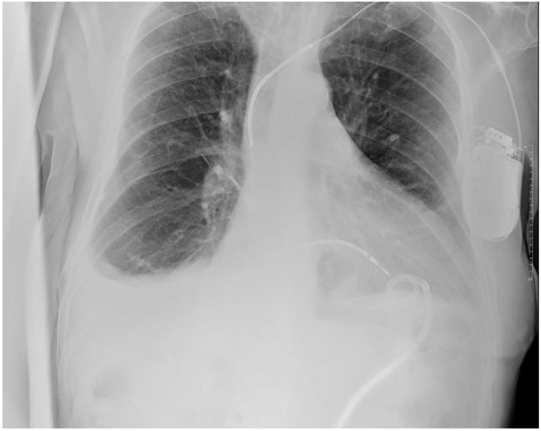

A 63-year-old male with a history of hypertension, dyslipidemia, GOLD C chronic obstructive pulmonary disease (COPD), and ICD-VR was referred from Cardiology to the Emergency Department after an echocardiogram showed a non-dilated inferior vena cava and a bilateral pleural effusion, predominantly on the left, with no apparent cardiac cause. The patient reported progressive dyspnea, a dry cough, and a 14 kg weight loss over the past year, without orthopnea, edema, or decreased urine output. On arrival, his baseline oxygen saturation was 91–92%. A chest X-ray confirmed the pleural effusion (Figure 1), which is why he was admitted to Internal Medicine for study.

Figure 1: Chest radiography in anteroposterior projection. There is cardiomegaly and bilateral pleural effusion without condensation images.